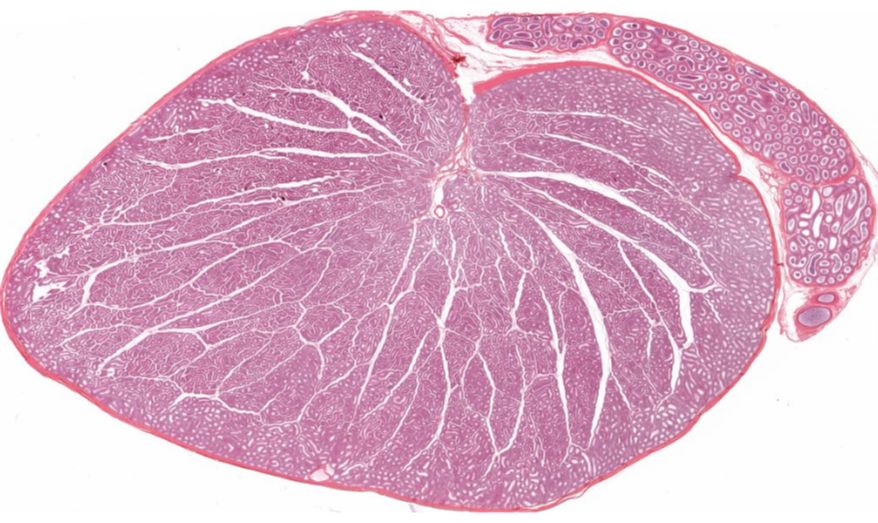

低倍镜:睾丸表面为鞘膜覆盖,其上皮为单层扁平上皮,鞘膜下是一层较厚的致密结缔组织,叫做白膜。白膜在睾丸后缘增厚,形成睾丸纵隔,其内可见不规则的腔隙,即睾丸网。睾丸内可见很多上皮性管道的切面,即生精小管的切面,呈圆形或椭圆形,管壁较厚,由生精上皮及其明显的基膜等组成。高倍镜:着重观察生精小管和其之间的睾丸间质。生精小管主要由生精上皮构成。生精上皮由生精细胞和支持细胞组成。生精细胞是一组细胞,依次自基膜向管腔面排列。

1.睾丸全景图

2.白膜

3.睾丸小叶

4.睾丸小叶间隔

5.生精小管